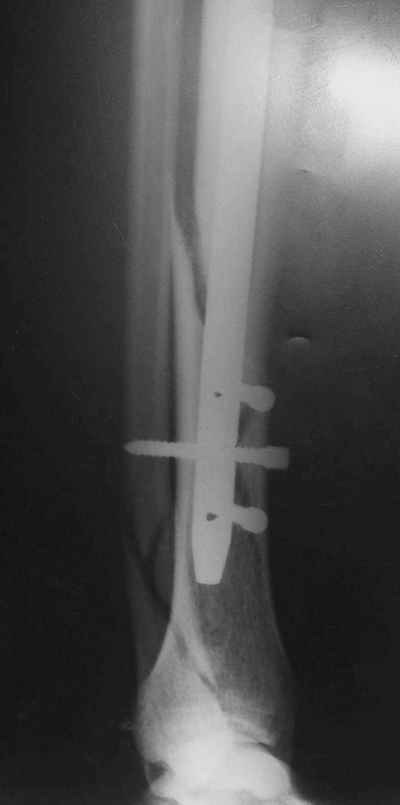

Потекло через месяц - открылось 2 свища по старому рубцу от давно удаленной пластины. На фоне гноя раза три завинчивал обратно винты, которые вылезали латерально, прямо через свищ. Потом таки провел дополнительно винты мимо гвоздя, и убрал вверху статический винт. Острый гнойный процесс стих, свищи мыла она дома дважды в день водным хлоргексидином, ходила с возрастающей нагрузкой, а к 10 мес. и свищи закрылись, и срослось. Итоговые снимки от 18 апреля 2003 г. прилагаю.

Рентгенограмы

Не удается отправить первичные снимки. А что скажите по имеющимся?!

Выполненный остосинтез нестабилен. Штифт надо заменить по "размеру" на солидный, дистльно три запирающих винта. Успехов!

Перелом спиральный, то есть низкоэнергетический, так что со сращением дело обстоит уже неплохо, лишь бы "костоеда" не развилась. Отломки выглядят уже стабилизированными костной мозолью, так что довводить винты, наверно, уже незачем. Разве что при клинической оценке подвижность еще есть - тогда можно для стабилизации наложить простейший аппарат, не опасаясь контакта его элементов с гвоздем, поскольку места в дистальном метафизе оставлено более чем достаточно.

С Александром согласен, нет необходимости делать дополнительные усилия для сращения, не большая компрессия аппаратом из двух колец и полная нагрузка доделает работу.

Потекли блокирующие винты.

Удалять их всё равно придётся.

Уже имеется какое-то сращение. А в этих условиях выполнить реостеосинтез гвоздём не дольше, чем "накинуть" аппарат из двух колец. Ходить можно сразу с полной нагрузкой, да и качество жизни пациента без аппарата лучше.